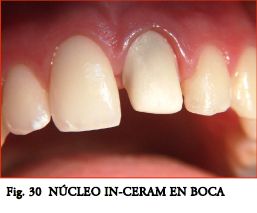

Hasta la aparición de los Postes Cerámicos, fabricados en base a Óx. de Circonio (ZrO), la posibilidad de lograr efectos ópticos similares a los dentarios era impensable. Los sistemas cerámicos no se han impuesto (entre otras causas) por presentar espesores poco conservadores y ser muy rígidos y estresantes con el riesgo de provocar fracturas radiculares intratables. Sin embargo los nuevos PPF conjugan excelentes propiedades estéticas con muy buenas propiedades mecánicas. Pueden ser “blanco opacos” para disminuir la sombra gris hacia la encía, o “blanco translúcidos” (Figs. 1, 2, 3, 5), para mantener la estética y permitir el pasaje de la luz de curado. Al eliminar la masa interna oscura de los postes metálicos se mejoran mucho las cualidades ópticas. Si bien en coronas metal-cerámica el efecto es inapreciable, es excelente en las cerámicas sin núcleo y para algunos autores también en algunas cerámicas de núcleo (In-Ceram).

APLICACIÓN DE LOS CONCEPTOS EN UN PROTOCOLO CLÍNICO.- Pieza 21.

Paciente de sexo femenino, 18 años de edad.

Antecedente de traumatismo en sector anterior a los 11 años. Presenta en la pieza 21 tratamiento de endodoncia, blanqueamiento y resina de fotocurado tipo carilla (Fig. 11) que se mantiene en control periódico.

Los requerimientos estéticos máximos, la posibilidad de un futuro retratamiento y las fuerzas moderadas existentes permiten indicar un sistema en base a PPF y corona total cerámica.

Elección del Poste.- Se elige un poste de Cuarzo liso de doble conicidad, D.T. Light-Post nº 1 (Fig.12) de acuerdo a la radiografía.